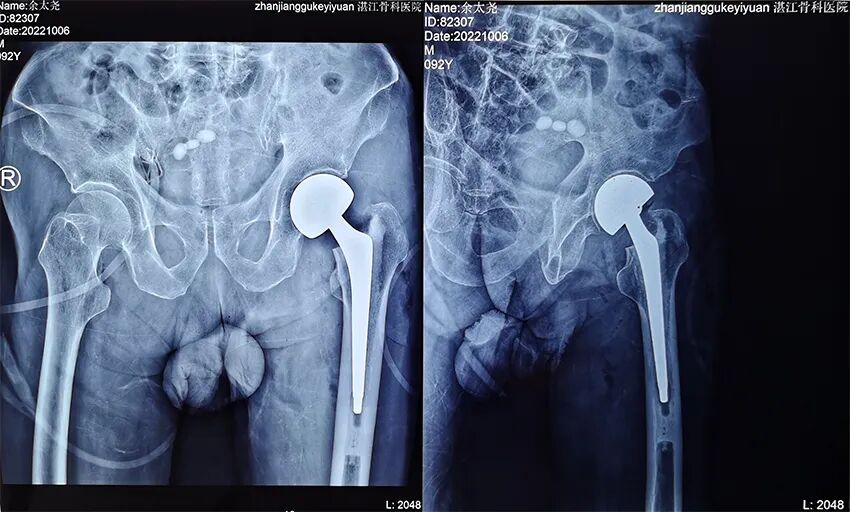

患者余某,男性,今年92岁,家住雷州纪家镇某村。

入院:2022年10月2日;出院:2022年10月19日。

术后图像